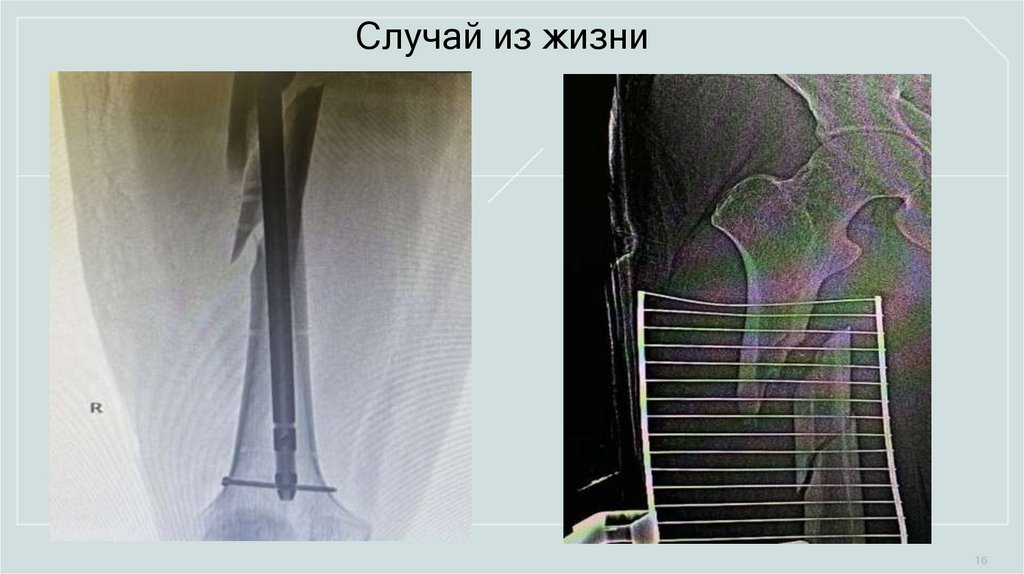

Случай из жизни

1.56M

16. Случай из жизни